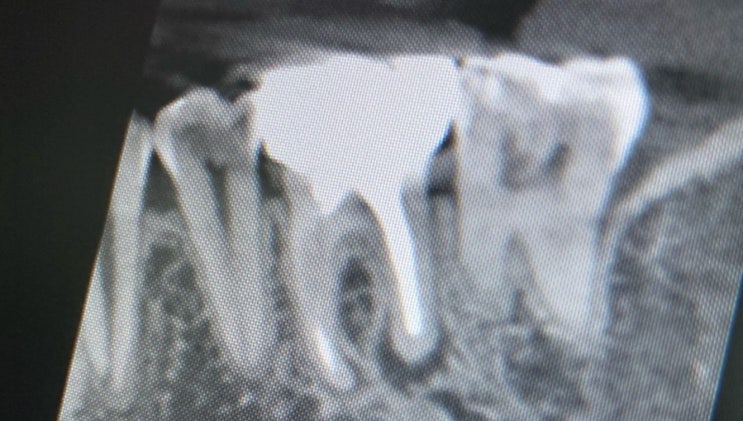

치과직원이 치과 치료받기

아이러니하지만 치과직원이 본인이 일 하는 곳에서 치과치료 받기 힘들다. 난 그 느낌을 잘 알아서 막내들 ...